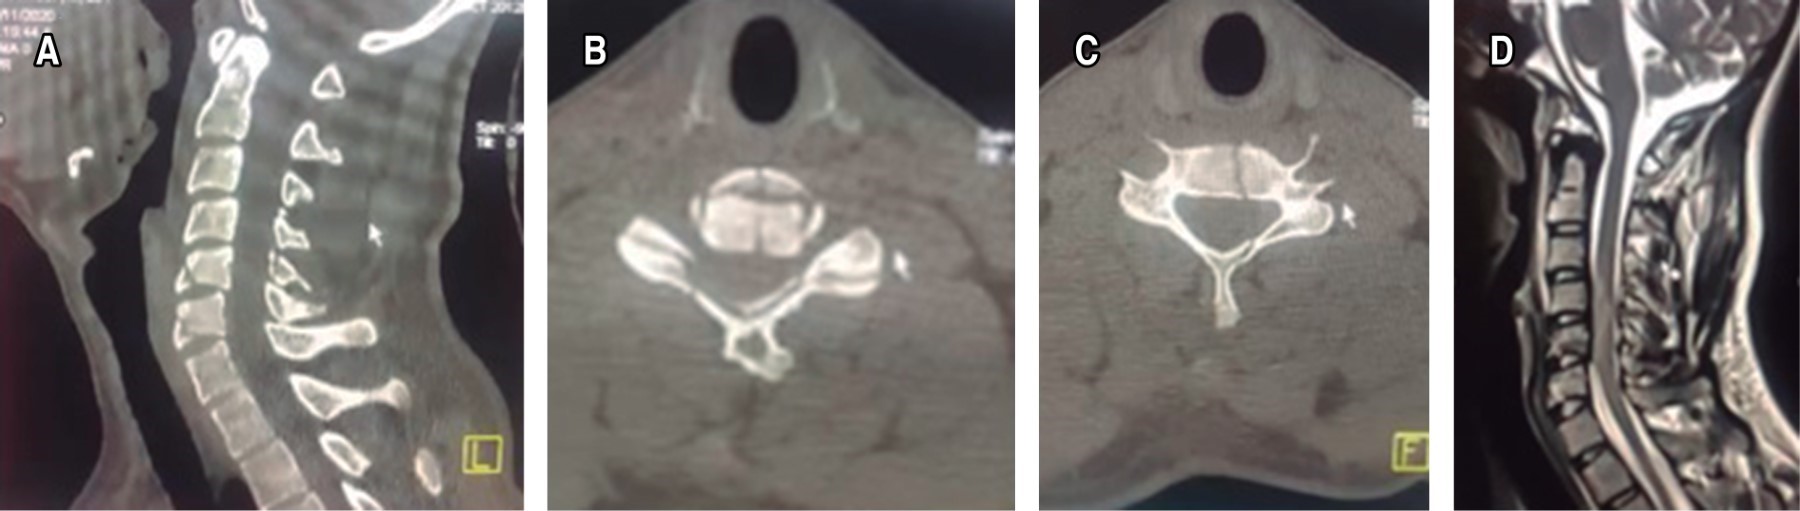

Posterior al interrogatorio y exploración física, se procede a solicitar estudios de gabinete con radiografías simples de columna cervical en proyecciones anteroposterior y lateral, así como tomografía axial computarizada, donde se observa desplazamiento anterior del cuerpo vertebral C5 sobre C6 e incongruencia articular facetaria mismos niveles. Se indica inmovilización con collarín rígido a permanencia en espera de realizar el complemento del estudio de imagen con una resonancia magnética nuclear simple de columna vertebral cervical corte sagital y axial T2 con presencia de compresión medular y lesión de complejo ligamentario posterior C5-C6. Se integra diagnóstico de luxación AO C5-C6:C (F4;N2;M1) ASIA D SLICS 5 y se procede a programar evento quirúrgico (Figura 1).

A los siete días después de su lesión, en primer orden se realiza el abordaje posterior con estabilización a masas laterales C4-C5 C5-C6, laminectomía C5-C6 y artrodesis posterolateral; se procede a efectuar un abordaje anterior con discectomía C5-C6 más fusión con caja intersomática tipo PEEK C5-C6 y placa anterior cervical, con una duración quirúrgica de tres horas 30 minutos para ambos abordajes y un sangrado reportado de 350 mililitros (Figura 2).

Paciente femenino de 66 años de edad, con diabetes mellitus tipo II, obesa e hipertensa de larga evolución; trasladada al sistema de urgencias de primer contacto tras sufrir accidente automovilístico tipo volcadura, ocupando el asiento trasero del copiloto sin cinturón de seguridad con pérdida de conocimiento referida por cinco minutos. Al momento del ingreso, durante la revisión primaria, se encuentra una paciente con escala de coma de Glasgow 12/15, sin compromiso de vía aérea, uso de collarín blando el cual es sustituido por collarín rígido, dolor en línea media cervical con sensación de escalonamiento, sin equimosis, extremidades superiores integras, con fuerza muscular C5-T1 3/5 bilateral, sensibilidad derecha C5-T1 1/2, izquierda C5-T1 2/2, ROTS hiporreflécticos, Hoffman negativo, reflejo pectoral de Bekhterev negativo, sin datos de inestabilidad clínica en pelvis, no se aprecian datos de bajo gasto cardiaco, extremidad inferior izquierda con fuerza muscular 3/5 de L2-S1, sensibilidad y ROTS presentes, extremidad inferior derecha con dolor, aumento de volumen ++ y crepito a la palpación en tercio proximal de pierna con pulsos distales presentes, tono de esfínter anal disminuido. Se realiza protocolo ATLS, se procede a solicitar valoración de neurocirugía con traumatismo craneoencefálico Marshall I y fractura luxación AO C6-C7:C (F4;N3;M1) evidenciada mediante tomografía axial computarizada clínicamente ASIA B (Figura 3); en revisión secundaria y con uso de estudios de imagen extendidos se reporta una fractura de meseta tibial derecha Schatzker VI AO 41C1.2, fractura diafisaria de peroné derecho AO 4F2b(a) y fracturas de arcos costales izquierdos 6, 7 y 8.

Se solicita resonancia magnética simple de columna vertebral cervical corte sagital y axial T2 con compresión medular a expensas de deslizamiento anterior al menos de 50% de cuerpo somático C6 sobre C7 con lesión de disco intervertebral C6-C7 y de complejo ligamentario posterior desde C6 hasta T1 SLICS 6 (Figura 3).

Se trata de paciente masculino de 26 años de edad que presenta accidente automovilístico por choque frontal, ocupa el asiento de copiloto, saliendo expulsado a través del parabrisas al no usar cinturón de seguridad, con pérdida del estado de alerta; es atendido de manera inicial por personal paramédico y es trasladado a medio particular en donde se realiza protocolo ATLS y valoración por cirujano de columna vertebral. A la exploración física con escala de coma de Glasgow 14/15, dermoabrasiones múltiples en cara, antebrazo y pierna derecha, dolor cervical en línea media, extremidades torácicas con fuerza muscular 3/5 de C5-T1, sensibilidad bilateral 1/2, ROTS +/+++, control de esfínteres, extremidades pélvicas fuerza muscular 1/5 de L2-S1, sensibilidad derecha 1/2 con cambios termoalgésicos en extremidad torácica izquierda, ROTS +/+++. Con base en los estudios de imagen iniciales se establece diagnóstico de fractura en lágrima AO C5-C6:C (N1;M2) ASIA C con contusión medular y lesión de complejo ligamentario posterior SLICS 6 (Figura 5).